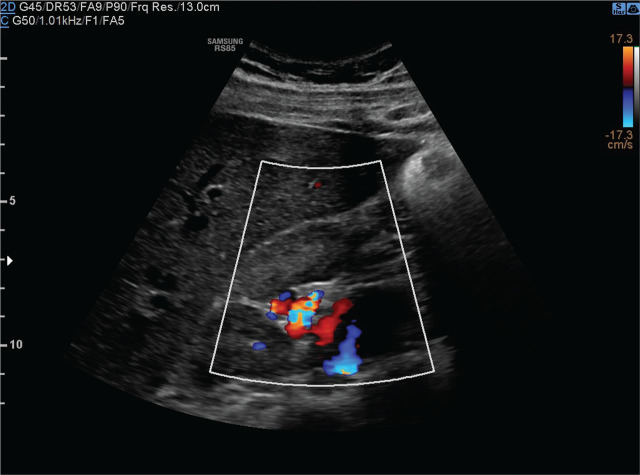

Case report: A 17-year-old boy complained of periodic abdominal pain. Abdominal ultrasonography revealed a multilocular cyst in the right kidney. Physical examination showed no abnormalities, and his blood pressure was 120/80mmHg. Abdominal ultrasonography showed a cyst measuring 36×30×25mm in the right kidney hilum. Computed tomography did not show the hepatic and suprarenal sections of the inferior vena cava. Numerous varicose-dilated collateral vessels, including renal venous vessels, were found in the right kidney hilum. The collateral vessels in the tomography matched the described in the ultrasound renal cyst. MRI confirmed IVCA with no other additional vascular abnormalities. Due to the risk of deep vein thrombosis of the lower limbs, non-pharmacological antithrombotic prophylaxis was recommended.